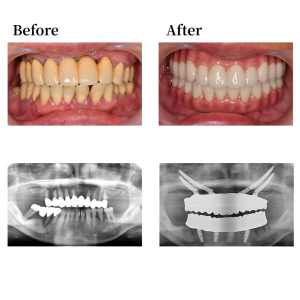

上顎骨の形状を整え、12、25の位置にザイゴマインプラントを52度傾斜埋入。22の位置にザイゴマインプラント45度傾斜埋入。15の位置にザイゴマインプラントを60度傾斜埋入。下顎も形状を整え、45, 42, 32, 35の位置にそれぞれオールオン4インプラントを埋入。 42, 32の位置に、0度垂直埋入、45, 35の位置に17度傾斜埋入。その後、マルチユニットアバットメントで角度補正を行い、プロビジョナルレストレーション(審美的な仮歯)を装着した。

上下顎はUTジルコニアで構成された、フルジルコニアブリッジでファイナルレストレーションとした。焼成されたジルコニアはステインテクニックで着色した。シェードカラーはA1。